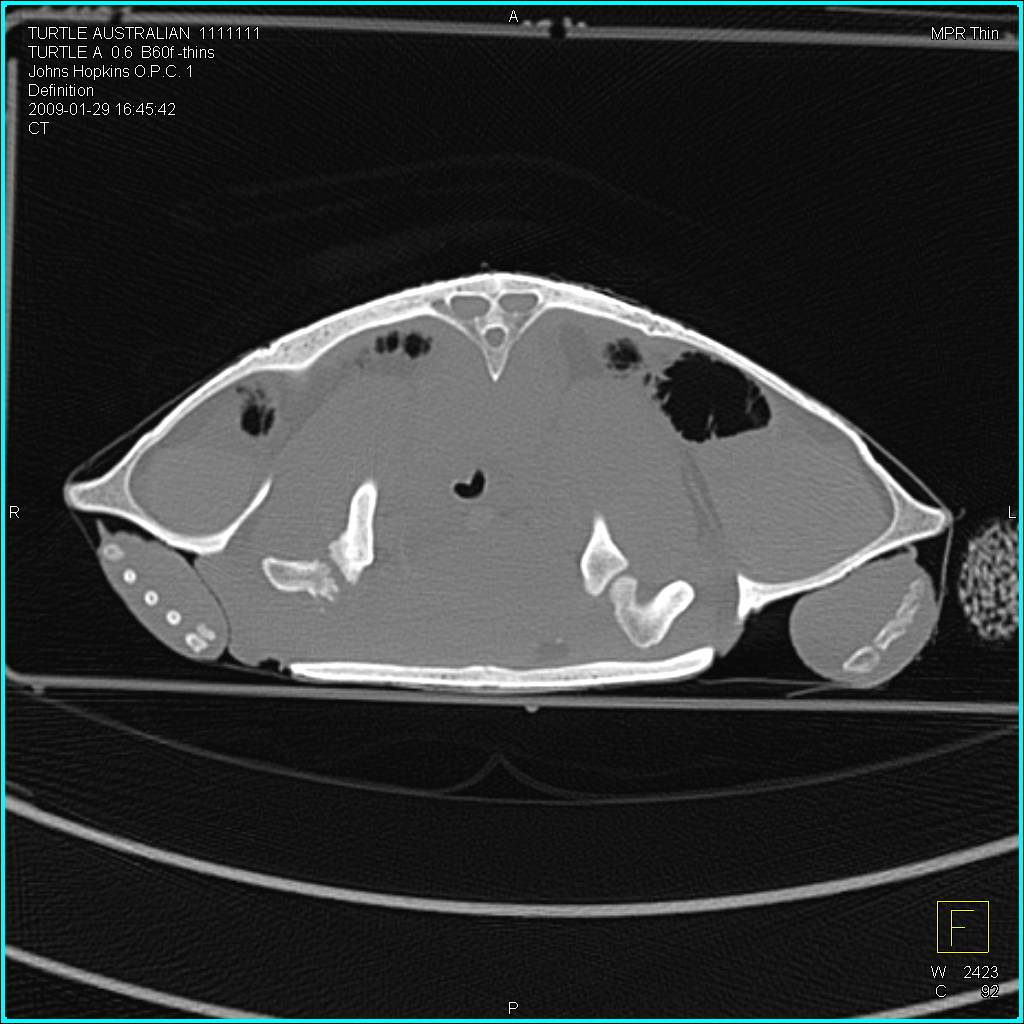

Ulceration Inner Right Thigh with Several 3D Rendering Techniques